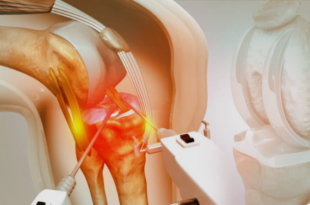

Knee pain hinders mobility and diminishes independence and quality of life. Robotic knee replacement in Chandigarh is the newest precise treatment option for patients battling severe arthritis or longstanding damage in their joints. At ARV Orthopedic Hospital Chandigarh, specialist surgeons in joint replacement provide world-class orthopedic services using modern robotic-assisted …

Knee pain can make everyday tasks like walking, climbing stairs, or even just standing up very uncomfortable. For people with severe arthritis or joint damage, knee replacement surgery is often the best way to fix the problem. Robots now help with this procedure, which makes it more accurate, speeds up …